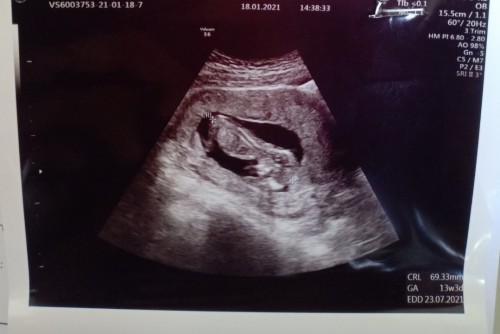

ซาวด์ 13 week น้องนอนคว่ำ ผิดปกติไหมคะ

สอบถามคะ ไปซาวด์มาเมื่ออาทิตย์ที่แล้ว อายุครรภ์ 13 week 3 day ตอนคุยกับหมอ หมอไม่ได้พูดอะไรเกี่ยวกับน้องนอนคว่ำ หมอพูดเรื่องทั่วไป แต่กลับบ้านมาให้คนที่บ้านดู เค้าถามว่าทำไมนอนคว่ำ เราตอบไม่ได้คะ ตอนใบซาวด์เราไม่ได้เอะใจทเลยไม่ได้ถามหมอคะ มีใครพอทราบบ้างไหมคะ ปล. หาหมอ รพ เลยติดต่อคุณหมอไม่ได้คะ #ขอคำแนะนำหน่อยค่ะ #ท้องแรกคะ #ขอบคุณสำหรับคำตอบค่ะ #ขอบคุณล่วงหน้านะคะ #ขอคำแนะนำค่ะ